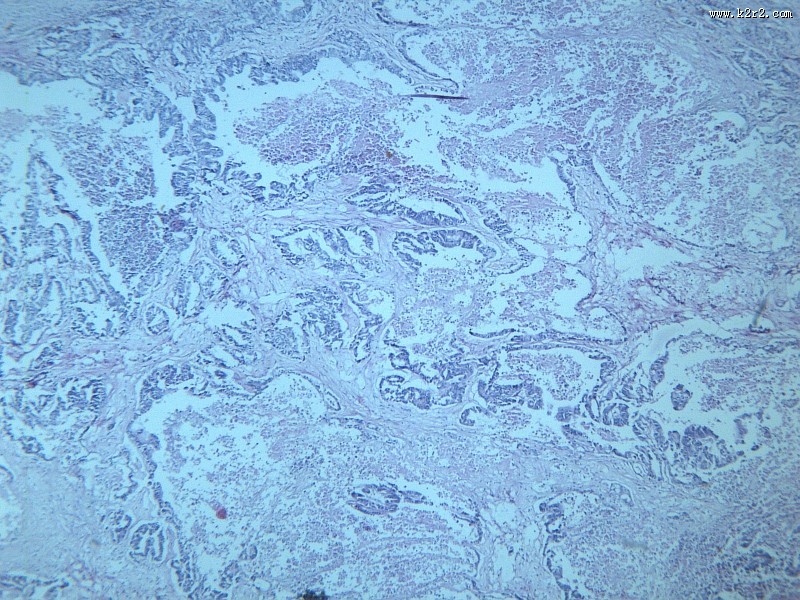

腺癌肝转移大全 - 第2张

第 2 / 12 张

腺癌肝转移大全

图集中 / 共有 12 张图片

腺癌

腺癌肝转移